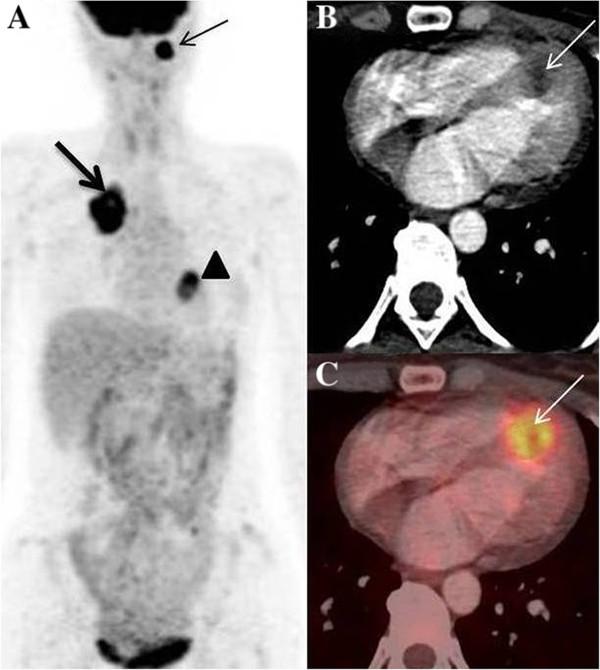

Asymptomatic myocardial metastasis from cancers of upper aero-digestive tract detected on FDG PET/CT: a series of 4 cases.

Metastatic involvement of the heart is a rare occurrence and remains undiagnosed until autopsy. In some instances, patients may have cardiac symptoms, leading to ante-mortem diagnosis. Although most primary cancers have been documented to metastasize to heart, the existing literature on cancers of upper aero-digestive tract is an exception, with only a few reports. We report four cases of upper aero-digestive tract cancers, three of which arise from oral cavity, one from lower esophagus, metastasising to the myocardium, detected on 18 F - Fluoro-deoxy-glucose Positron Emission Tomography/Computed Tomography (FDG PET/CT) study , in the absence of related symptoms.